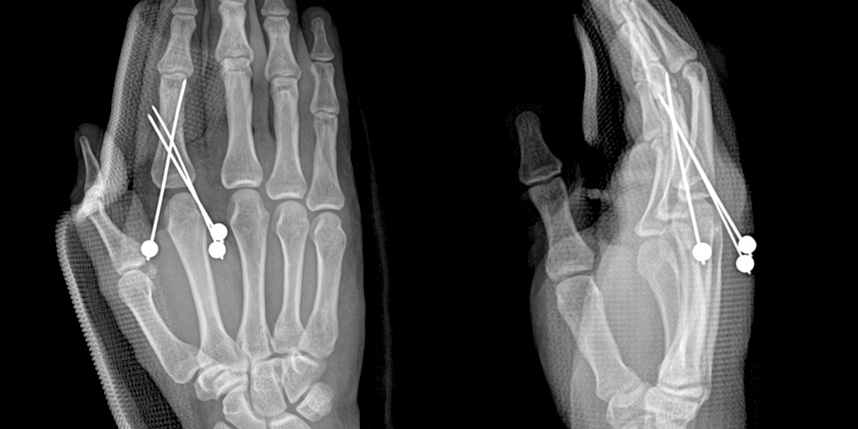

손가락 골절

* 환자에게 받은 소중한 자료입니다.